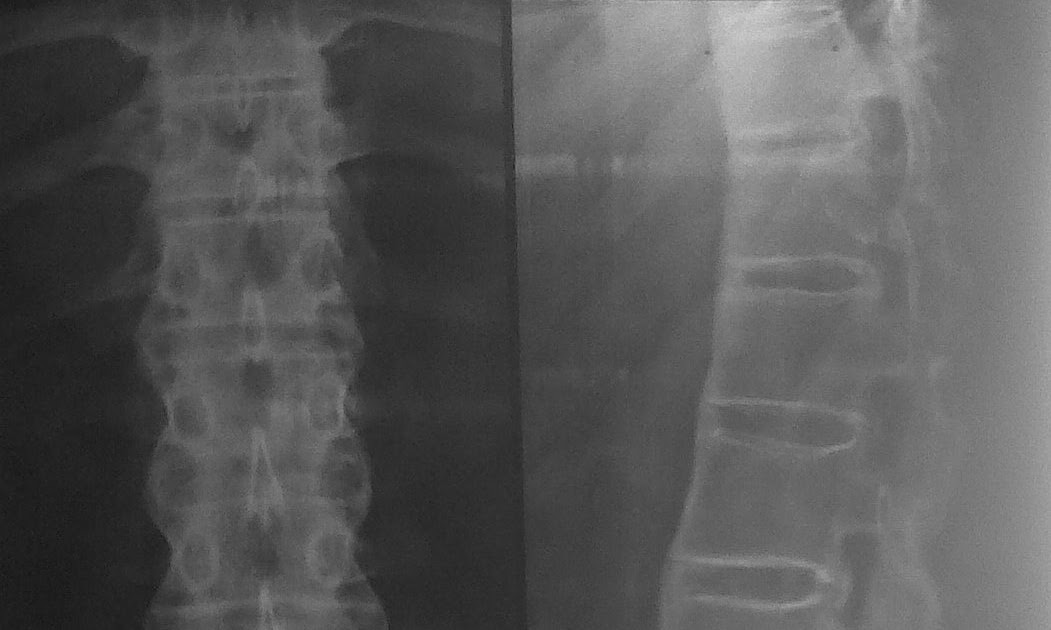

Medical Definition For Bamboo Spine . ankylosing spondylitis, also known as axial spondyloarthritis, is an inflammatory disease that, over time, can cause some of the bones in the spine,. ankylosing spondylitis (as) is an inflammatory disease that affects the joints and bones of the spine. it causes a decreased range of motion and, in its advanced stages, can give the spine an appearance similar to bamboo, hence the. bamboo spine is a complication of ankylosing spondylitis, which is a chronic inflammatory condition. ankylosing spondylitis (as) is a type of arthritis that affects the joints in your spine. It gives the spine a very symmetrical and segmented appearance. bamboo spine is a pathognomonic radiographic feature seen in ankylosing spondylitis that occurs as a result of vertebral body fusion by. bamboo spine is a term that refers to a specific spinal condition characterized by the fusion of the. ankylosing spondylitis (as) is a chronic form of inflammatory arthritis that primarily affects the spine, causing back pain and stiffness. bamboo spine is a characteristic finding seen in patients with as, which is a result of vertebral body. learn about this inflammatory disease that can cause some of the vertebrae in the spine to fuse over time. doctors refer to this finding as a bamboo spine appearance. Progression of the erosions leads to widening of the. bamboo spine is a pathognomonic radiographic feature seen in ankylosing spondylitis that occurs as a result of vertebral body fusion by marginal. the meaning of bamboo spine is a spinal column in the advanced stage of ankylosing spondylitis especially as observed in an x.

bamboo spine is a pathognomonic radiographic feature seen in ankylosing spondylitis that occurs as a result of vertebral body fusion by. learn about this inflammatory disease that can cause some of the vertebrae in the spine to fuse over time. Progression of the erosions leads to widening of the. in its advanced stages, ankylosing spondylitis (as) can lead to a condition that is sometimes called bamboo spine. This process tends to be. ankylosing spondylitis is a chronic seronegative autoimmune spondyloarthropathy characterized by. bamboo spine is a term that refers to a specific spinal condition characterized by the fusion of the. ankylosing spondylitis (as) is a type of arthritis that affects the joints in your spine. these syndesmophytes frequently bridge adjacent vertebrae, resulting in impaired spinal mobility. the meaning of bamboo spine is a spinal column in the advanced stage of ankylosing spondylitis especially as observed in an x.

BAMBOO SPINE ANKYLOSING SPONDYLITIS Medical Definition For Bamboo Spine ankylosing spondylitis is the prototypical spondyloarthropathy and a systemic disorder characterized by inflammation of the axial. doctors refer to this finding as a bamboo spine appearance. It usually develops in your sacroiliac joints (where. Progression of the erosions leads to widening of the. bamboo spine is a pathognomonic radiographic feature seen in ankylosing spondylitis that occurs as. Medical Definition For Bamboo Spine.